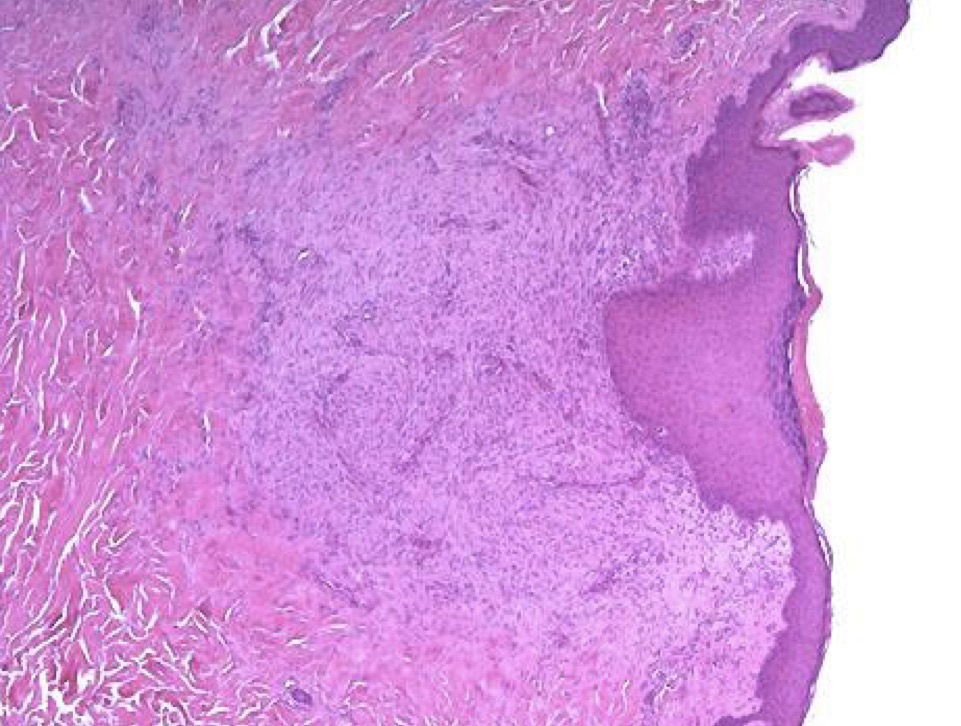

A- identify

B- describe

A- typical Tuberculosis Granuloma

B- area of central necrosis surrounded by multiple langhan type giant cells , epithelioid cells , lymphocyte